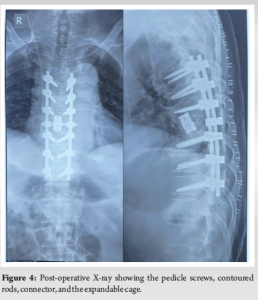

Pedicle screws were placed at the T5, T6, T7, T9, T10, and T11 levels. An expandable cage was inserted at the T8 level along with contoured rods and an interrod connector to provide spinal stability (Fig. 4).